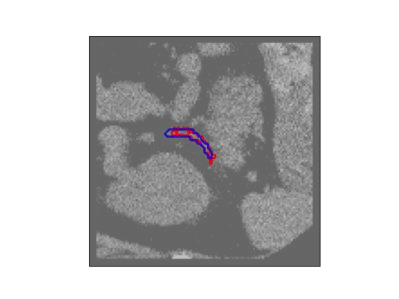

The human annotations are imperfect, especially when produced by junior practitioners. Multi-expert consensus is usually regarded as golden standard, while this annotation protocol is too expensive to implement in many real-world projects. In this study, we propose a method to refine human annotation, named Neural Annotation Refinement (NeAR). It is based on a learnable implicit function, which decodes a latent vector into represented shape. By integrating the appearance as an input of implicit functions, the appearance-aware NeAR fixes the annotation artefacts. Our method is demonstrated on the application of adrenal gland analysis. We first show that the NeAR can repair distorted golden standards on a public adrenal gland segmentation dataset. Besides, we develop a new Adrenal gLand ANalysis (ALAN) dataset with the proposed NeAR, where each case consists of a 3D shape of adrenal gland and its diagnosis label (normal vs. abnormal) assigned by experts. We show that models trained on the shapes repaired by the NeAR can diagnose adrenal glands better than the original ones. The ALAN dataset will be open-source, with 1,594 shapes for adrenal gland diagnosis, which serves as a new benchmark for medical shape analysis. Code and dataset are available at https://github.com/M3DV/NeAR.